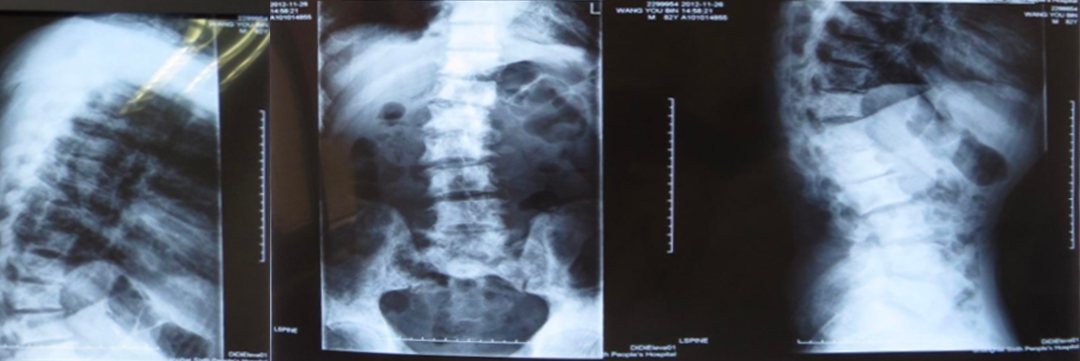

2、利用X线平片发现椎体压缩性骨折(每个医院包括社区均有):

脆性骨折是指受到轻微创伤或日常活动中即发生的骨折,老年男性椎体骨折的患病率与女性相当,椎体骨折的防治在男女两性同等重要。

常规进行X线胸腰椎正侧位摄片漏诊率高,患病率高(上海社区60岁以上17%,建议对50岁以上腰背部疼痛者常规摄片,及早发现椎体骨折。

二、骨质疏松症如何进行影像学检查

X线平片是检出脆性骨折,特别是胸、腰椎压缩性骨折的首选方法。常规胸、腰椎X线侧位摄片的范围应分别包括胸4至腰1和胸12至腰5椎体,基于胸、腰椎侧位X线影像并采用Genant目视半定量判定方法,椎体压缩性骨折的程度分类如下:

X线检查:胸腰椎多发压缩性骨折伴骨质疏松。

诊断:低磷性骨软化(肿瘤性可能)、继发性甲状旁腺功能亢进。

X线检查:L2压缩性骨折椎体骨质疏松,头颅未见异常。